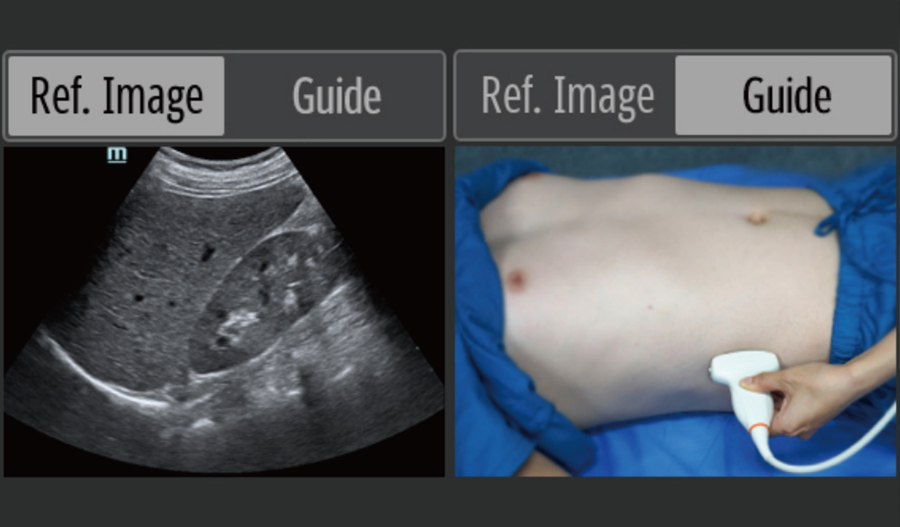

Point-of-Care-Ultraschall (POCUS)

Die integrierten Ultraschallfunktionen verbessern die Diagnose vor Ort erheblich. Dank der intelligenten Bedienungsanleitung k?nnen effiziente Ma?nahmen einfacher ergriffen werden.

- Referenzbilder und Bedienungsanleitungen

- Phased-Array-Sonde: hohe Aufl?sung, weit verbreitet